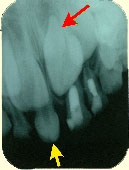

左の写真では乳歯が抜けて過剰歯(黄色い矢印)がはえています。レントゲンを撮影してみると過剰歯の下から永久歯が生えようとしています。このままでは過剰歯がじゃまをして永久歯が生えないか、生える方向が悪くなり歯並びに影響が出てきます。レントゲンではもう一本、顎の骨の中に過剰歯(赤い矢印)が見つかりました。顎の骨の中にある過剰歯は上下逆さまになっています。上下逆さまになっている過剰歯は自然に生えてくることはありません。永久歯に影響を与えそうな場合には抜く必要があります。隣りの写真が実際に抜いた過剰歯です。